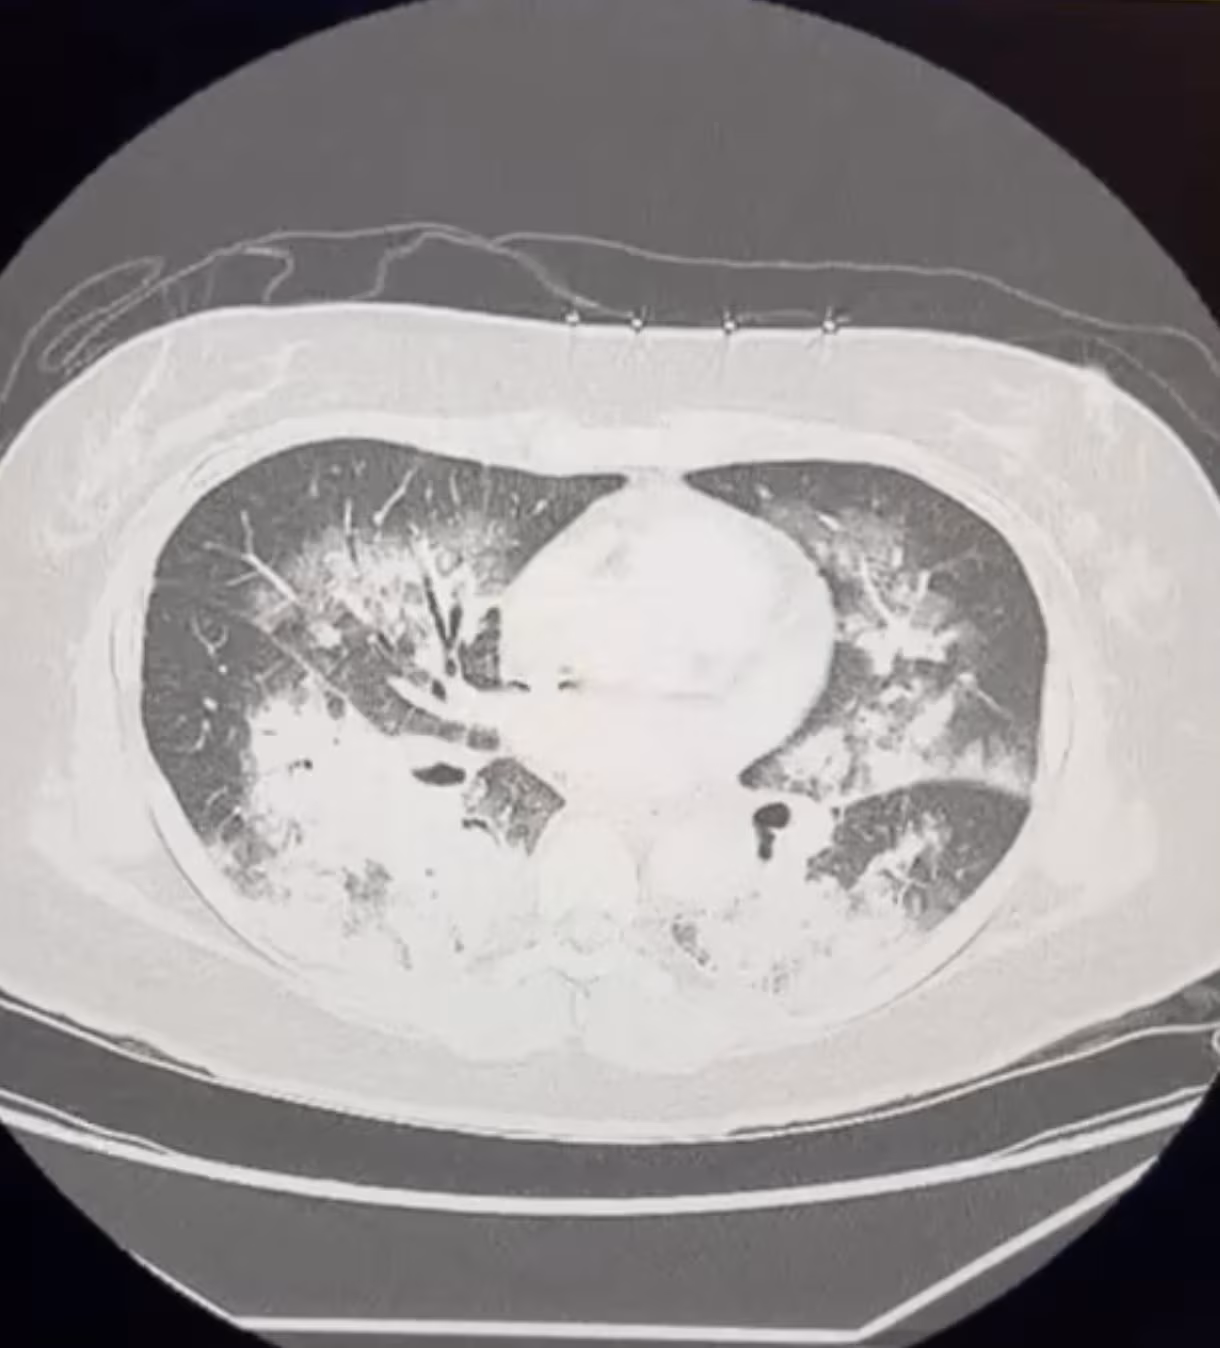

High altitude pulmonary edema (HAPE) typically shows up in otherwise healthy patients after rapid ascent (e.g., mountain-climbing) with subsequent coughing,…